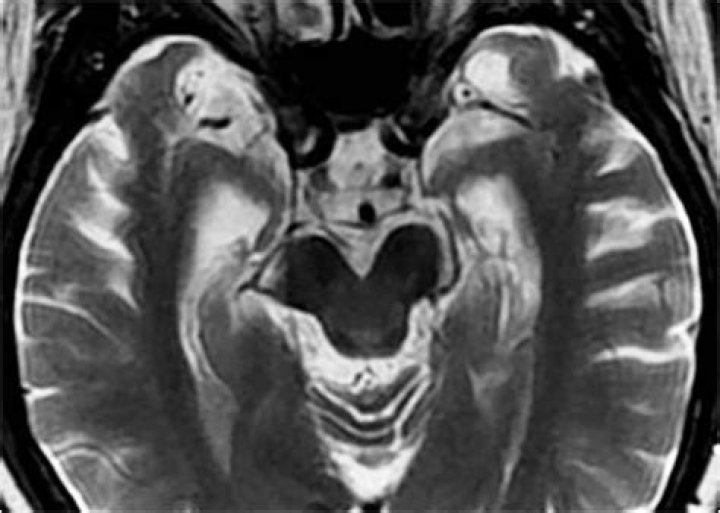

Alzheimer's disease is a progressive neurological disorder that affects memory, thinking, and behavior. It is the most common form of dementia, accounting for 60-80% of cases. Alzheimer's disease is caused by the accumulation of amyloid plaques and tau tangles in the brain. These plaques and tangles disrupt the normal functioning of the brain, leading to the symptoms of Alzheimer's disease.

Diagnosis typically involves a comprehensive medical history, physical and neurological examinations, cognitive tests, and brain scans.